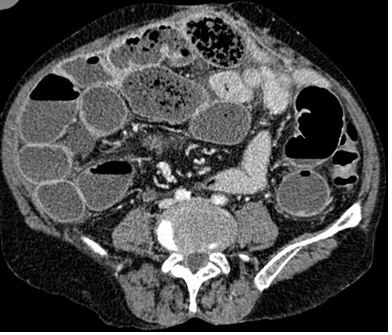

82세 여성이 3일 전부터 복부 팽만감을 호소하며 가스 배출이 없고 대변을 보지 못했다. 6년 전 대장암 수술로 인한 일부 대장 절제술을 시행받았다. 혈압은 128/80 mmHg, 맥박은 76회/분, 체온은 37.2℃로 측정되었다. 복부는 팽만해 있었지만, 특별한 압통이나 반발압통은 관찰되지 않았다. 복부 X선 및 CT를 통해 진단을 시도하였다. 적절한 치료 방법은 무엇인가?

AXR, APCT: stepladder sign

Imp: 소장폐색(small bowel obstruction)

• 복부팽만, 변비를 호소하는 환자의 AXR, APCT상 stepladder sign 및 small bowel dilatation이 관찰되어 소장폐색으로 진단할 수 있다.

• 환자의 복부 수술력(대장암 수술)으로 인한 adhesion이 장폐색의 원인일 가능성이 높다.

• V/S stable하고 압통, 반발압통이 관찰되지 않아 교액의 가능성은 낮고, 따라서 응급 수술을 진행할 필요는 없다.